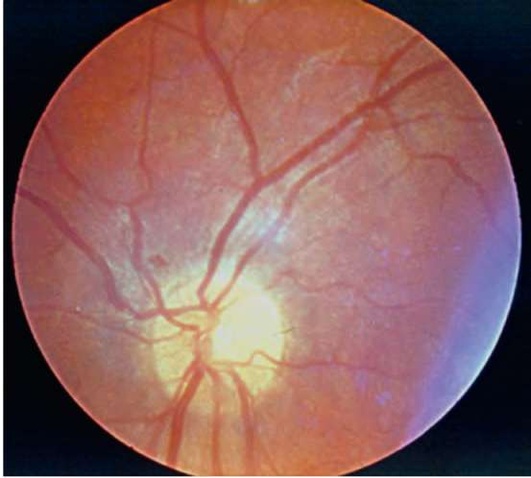

Рис. 12.1. Глазное дно. Норма